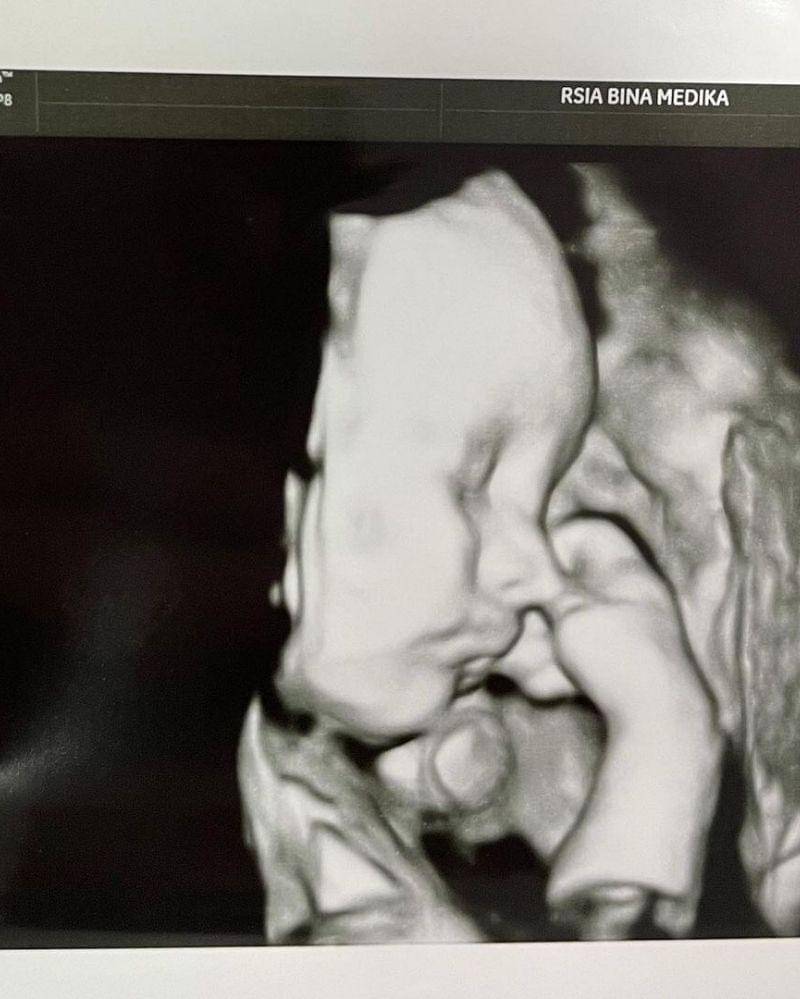

Kabar bahagia datang dari pasangan artis Audi Marissa dan Anthoni Xie yang telah menyambut kelahiran anak pertama mereka, pada Rabu (7/4/2021) lalu.

Bayi dari Audi Marissa lahir dengan kondisi prematur dan memerlukan perawatan intensif. Walau begitu, saat ini perempuan tersebut sudah bisa memberikan metode kanguru atau kangaroo mother care kepada bayinya.

Hal ini lah yang dilakukan oleh Audi Marissa yang melahirkan bayi prematur di usia kehamilan 31 minggu.